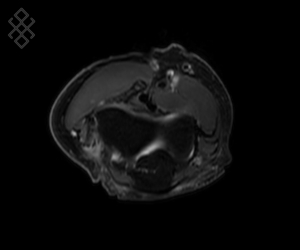

IRM du Coude

Vous entrez dans l'aimant, ouvert des 2 côtés, la tête la première et allongé sur le dos avec les bras le long du corps. Pour recueillir le signal et construire les images, vous aurez le coude dans une antenne. Étant donné que cet examen est bruyant, vous aurez à votre disposition des tampons auriculaires pour atténuer le bruit de la machine.